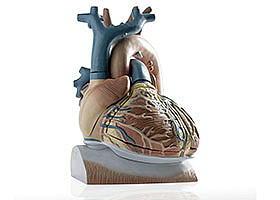

- Medicine and healthcare

- Simulation and data processing

- Software and IT

- Automation / IT

- Measurement technology

Heart models for the treatment of atrial fibrillation

Individual, digital heart models can be used to test therapies in order to select the one that promises the greatest success. A KIT method creates patient-specific virtual images of the heart from clinical data.